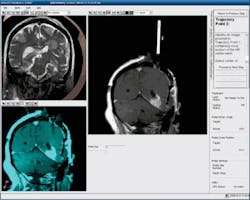

FIGURE 1. Within an MRI suite, a surgeon can operate the AutoLITT workstation to control the system's MRI-compatible laser therapy tools. Once the patient is positioned so that his/her head remains steady inside the MRI coil, a small opening is made in the patient's skull. The patient-probe interface (PPI) then establishes laser probe trajectory and provides stability during probe alignment, insertion, and operation.

FIGURE 2. A set of real-time images, generated during the initial stages of a LITT procedure, shows how the surgeon confirmed probe alignment, starting with two different views of a patient's brain (upper and lower left). At right, the alignment/confirmation wand, filled with MR contrast, highlights the planned trajectory.

The AutoLITT System, a LITT implementation by Monteris Medical (Winnipeg, MB, Canada), is a platform comprising MRI-compatible laser components that enable guided delivery of precision thermal therapy (see Fig. 1). The system received FDA 510(k) clearance in 2009 for use in neurosurgery. It promises another option to some brain tumor patients that may otherwise be unsuitable candidates for craniotomy or SRS. The system allows for conformal laser thermocoagulation of deep-seated brain tumor using a probe whose rotation and depth are surgeon-controlled, and it provides real-time quantitative temperature maps and thermal dosage zones (see Fig. 2), which predict therapeutic target tissue death.